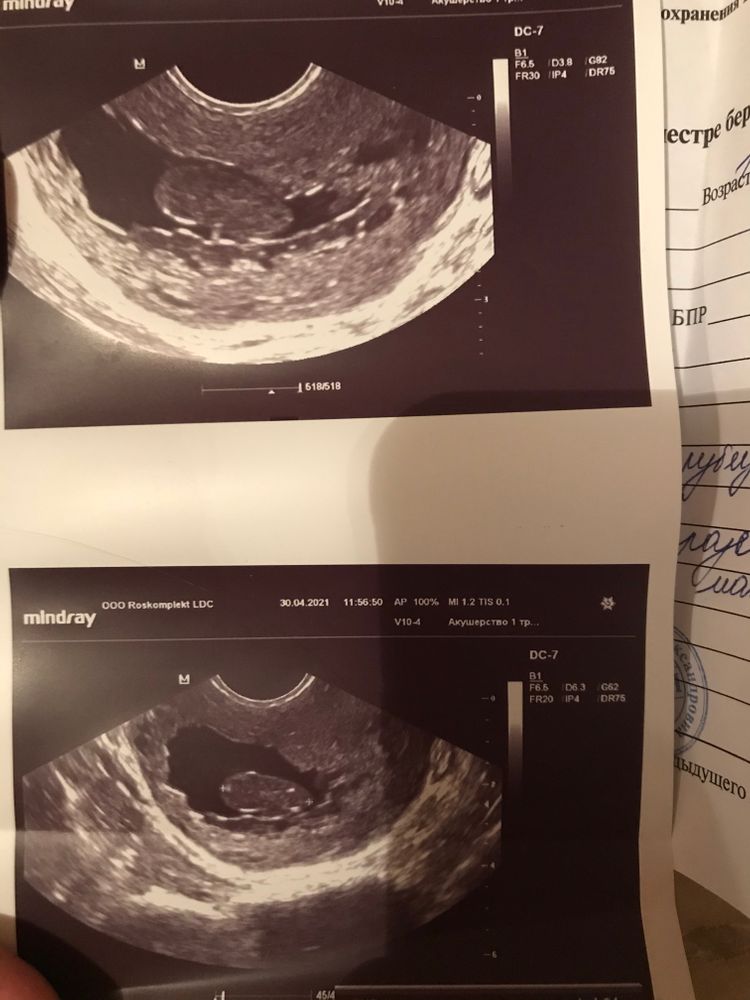

Полип или Б?

Врач сказала, что зб, срок 8 недель, но врач конкретно в моем случае лицо заинтересованное...долго рассказывать почему.

кто разбирается в узи, похоже ли это на полип или миому матки?

На миому очень похоже. Полип он ярко белый будет на узи. На ПЯ не особо, не видно хориона

Ангелина, 43 мм

Лолита Ананасова, ну вряд-ли миома могла за пару месяцев вырасти до таких размеров.

Ангелина, только что была на узи у более компетентного врача , как итог - это действительно пя, без эмбриона, сроком 8-10 недель которое не гниет так как активно кровоснабжается, даже очень хорошо, возможно, это все таки второе пя из двух, но в любом случае, оно осталось в результате некачественного мини аборта....скорее всего эмбрион вышел со сгустками и мазней, которая меня преследовала все эти месяцы, а пя осталось, а поскольку оно кровоснабжается, то не начинается выкидыш. Чистка будет однозначно, но из-за этих чертовых праздников очень большой вопрос , когда именно это случится.

Это все таки плодное яйцо, которое не было уделено во время мини аборта в 5 недель. Ещё 3 недели оно сражалось за жизнь и развитие прекратилось в 8 недель. 3 месяца я ходила с этим и даже не подозревала. Лежу в стационаре на скорой, надеюсь все будет хорошо.

Не похоже это ни на какую миому

"Чёрное" вокруг на УЗИ - это всегда жидкостной компонент

Это картина ЗБ. С выраженной деформацией плодного яйца

И хорион я не вижу здесь